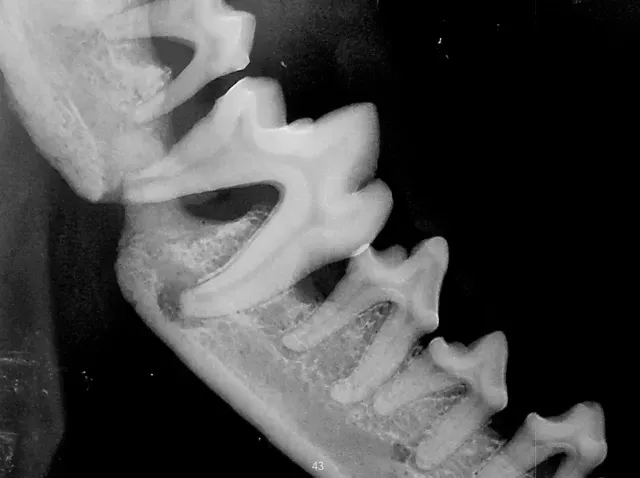

Pet dental X-rays are an important diagnostic tool that allow veterinarians to assess the health of teeth and surrounding structures beneath the gumline when required.

Many dental problems, such as tooth root infections, fractures, and bone loss, are not visible during a standard oral examination. In cases where there is concern about underlying disease, dental X-rays can provide detailed images of each tooth’s root and surrounding bone, helping to identify issues that cannot be seen on the surface.

By detecting problems beneath the gumline, dental X-rays assist veterinarians in making informed decisions regarding extractions, treatment options, or ongoing dental care.

Dental X-rays are not routinely performed for every dental procedure and are recommended on a case-by-case basis where they will add clinical value. When advised, they help ensure underlying issues are properly identified and managed, supporting your pet’s long-term oral health.